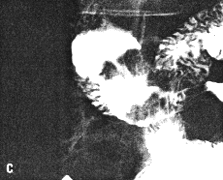

Case 33.7 M.B., 68 year old female, presented with a large, hard epigastric mass. Radiology showed a constant narrowing of the distal 3.0 to 4.0 cm of the stomach, somewhat resembling partial contraction or spasm of the pyloric sphincteric cylinder (Fig. 33.7A). However, it contained a filling defect and mucosal folds were absent. While some degree of movement was seen, this was atypical, with total absence of cylical contraction and relaxation of the cylinder (Fig. 33.7B - E). The base of the duodenal bulb appeared normal. Emptying of barium suspension was not significantly delayed.

At Billroth II partial gastrectomy a large, ulcerated pyloric carcinoma, extending aborally as far as the pyloric ring, was removed. The duodenum appeared normal. Microscopy revealed a signet ring cell carcinoma extending as far as the lamina propria and not involving the muscularis. The duodenum was confirmed to be normal.

![]() |

| Fig. 33.7. A Case M.B. Narrowing distal 3.0 to 4.0 cm of stomach resembling partial contraction or spasm of sphincteric cylinder. |

![]() | |

| Fig. 33.7 B-E. Case M.B. Filling defect in narrowed region. Mucosal folds absent. Some movement evident but cyclical contraction and relaxation of sphincteric cylinder absent. Base of duodenal bulb appears normal. | |